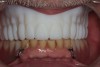

The patient was a 70-year-old man who worked as a dental laboratory technician. He presented because his long-standing maxillary denture was worn and had become ill-fitting. In the mandible, he wore a partial denture. A plan was developed to restore his edentulous maxilla (Figure 1) with a new denture that was digitally designed and fabricated using CAD/CAM technology.

Figure 1 The edentulous maxilla.

Figure 1